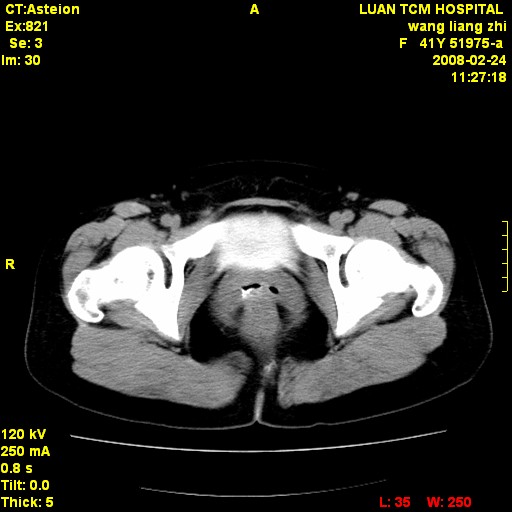

以下是引用dyqct在2009-8-23 16:17:00的发言:[br]考虑:1、造影剂进入腹腔、结肠旁沟、肝周;[br] 2、子宫明显增大(腺肌增生症?);[br] 3、膀胱显影是由于造影剂吸收后经肾分泌进入膀胱的;[br] 4、建议mri检查子宫。